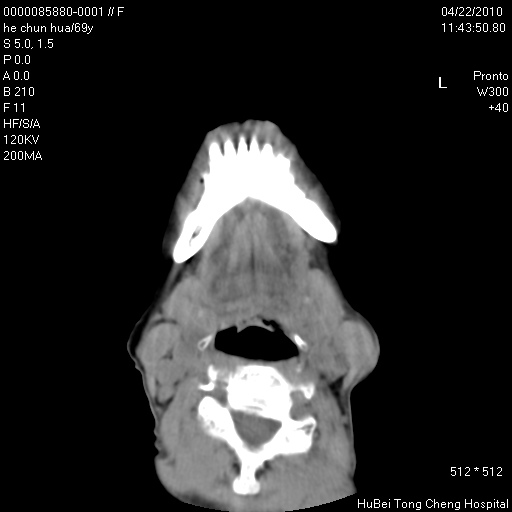

标题: CT25937:女,69Y

硬腭部包块十余年,渐进性增大。